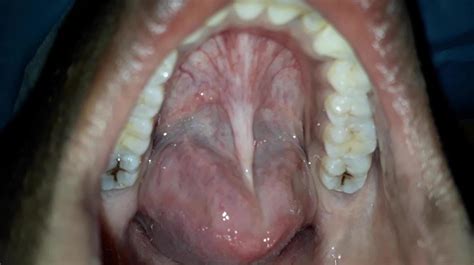

Experiencing a uvula touching tongue sensation? Discover the common causes behind this throat irritation, including swollen uvula, enlarged tonsils, or acid reflux. Learn about effective home remedies, symptom management, and when it is time to consult a doctor for persistent throat discomfort or difficulty swallowing. Understand your symptoms and find relief from this annoying oral sensation today.